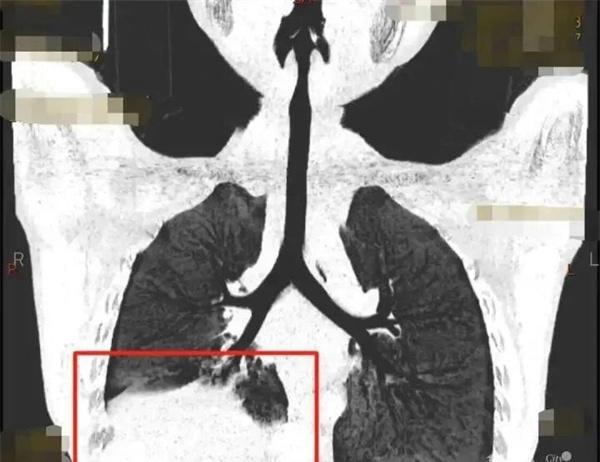

6歲小男孩發燒11天時間都不退,經過CT檢查發現孩子肺部已經有了很嚴重的感染,已經要痰栓阻塞了,就像一根根樹枝一樣,不處理對于肺部功能會有較為嚴重的影響。之所以有痰栓阻塞,是因為有塑形性支氣管炎的患兒,在氣道炎癥的分泌物過于粘稠,長時間沒有辦法將這些分泌物咳出,就會成為膠凍狀的痰栓在支氣管內部堵塞。

順利將碳酸全部取出后,小男孩在呼吸內科接受了抗感染的治療以及激素的治療,肺部的感染狀態,也在逐漸好轉。因為治療不夠及時的原因,這一次感染給身體也留下了無法避免的創傷,肺炎支原體肺炎所引起痰栓這種狀況是有的,但并不是高發的情況。如果一直高燒都不退的話,一直咳嗽且不斷的發熱在肺部,影像提示有著較為厲害的病變,不及時發現治療的話是很容易有痰栓形成的,具體根據孩子的病情作出判斷。